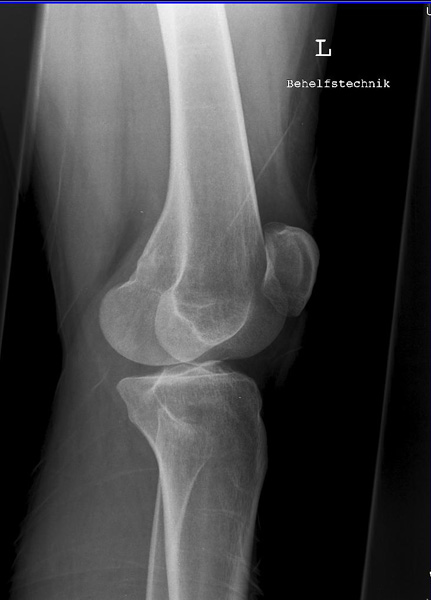

Knie seitlich

126_3.jpg

Fehler

Die Femurkondylen stehen nicht senkrecht übereinander. Zudem wird die Patella vom lateralen Anteil der Femur und das Fibularköpfchen vom Tibiakopf überdeckt.

Abhilfe

Abhilfe bringt eine weitere Drehung des Patienten nach vorne in Richtung Patella, damit die Kondylen wieder übereinander liegen.